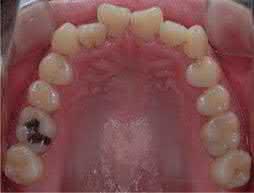

A moderate to severe dental open bite, often in conjunction with a skeletal open bite, is regarded as one of the most challenging orthodontic problems to correct. The main applications of TADs for correcting anterior open bite are either intrusion of the posterior teeth or extrusion of the anterior teeth. For molar intrusion, TADs have been placed in various anatomical sites [20–22].

For open bite correction, TADs can be combined with a transpalatal arch (TPA) to provide efficient maxillary posterior tooth intrusion along with tongue exercise (Figure 1.6) [20]. Anterior open bite also can be corrected with TADs and miniplates (Figure 1.7) [21]. Miniplates were placed bilaterally in the zygomatic arch and the mandibular molar regions to provide absolute anchorage for bimaxillary molar intrusion. This approach can not only treat dentoskeletal open bite with positive overbite but can also achieve a counterclockwise rotation of the mandible. In lingual orthodontics, palatal

Figure 1.4  Comparison between a palatal anchorage plate and buccal TADs [14, 15]. (a) A palatal anchorage plate was placed for maxillary total arch distalization. (b) TADs were placed on the buccal side of the posterior teeth. (c) The palatal anchorage plate group showed greater distalization and greater intrusion with less distal tipping of the maxillary first molar and more extrusion of the maxillary incisor than the buccal TAD group. (d) No significant changes were found in the airway volume or minimum cross-sectional area of the oropharynx after treatment with these two groups.

TADs can be used to retract the anterior dentition and intrude the posterior dentition to correct anterior open bite (Figure 1.8) [22]. One advantage of this modality is that the proclination and intrusion of the maxillary anterior teeth can be controlled by adjusting the length of the crimpable hooks and the vertical locations of the palatal TADs (Figure 1.8c).